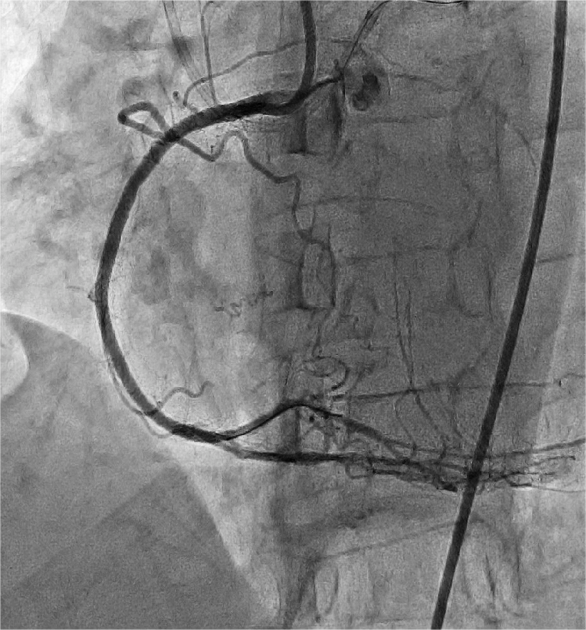

4月24日,朱舜明副主任医师为患者制定周密的手术方案和风险处理方案,朱舜明副主任医师、唐治国主治医师、张翔主治医师、张豪住院医师开展持续3小时的介入手术。术中穿刺桡动脉和股动脉,双路径同时造影显示病变血管完整结构,开展Reverse-CART技术,将逆向导丝送入正向指引导管,跟进微导管,交换导丝后用球囊扩张病变,沿逆向导丝送入双腔微导管至闭塞血管远端,沿双腔微导管送入正向工作导丝至右冠后降支,并退出逆向微导管和导丝,采用血管内超声精细评估病变情况,最终向右冠状动脉内植入3枚支架。术后多体位造影未见残余狭窄及贴壁不良,完美结束手术。

图4 造影提示血流恢复